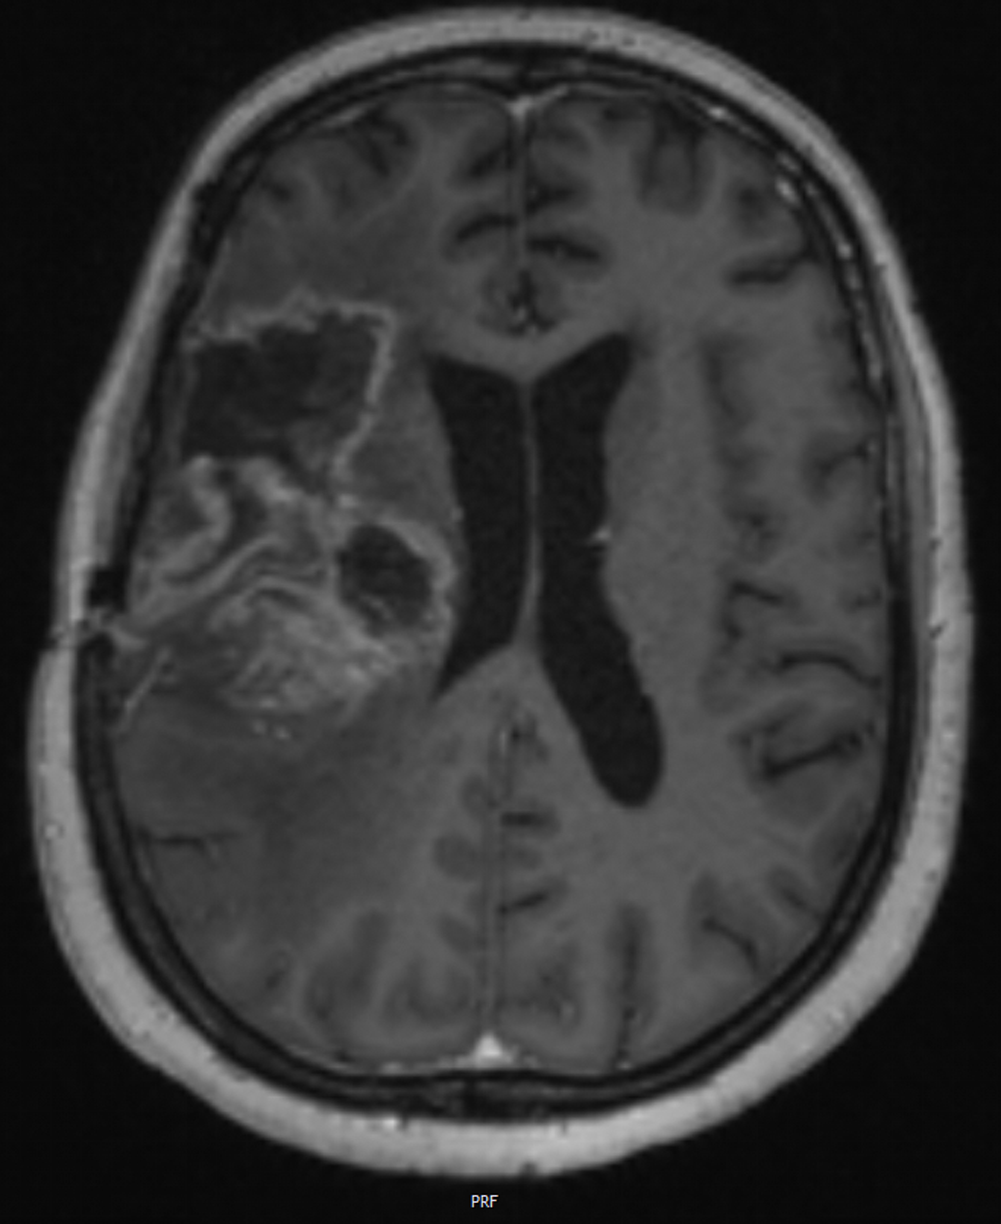

Ebenso bot es die Chance, mittels serieller Magnetresonanztomographie (MRT)-Bildgebung Merkmale zu identifizieren, die ein Therapieansprechen vorhersagen können. Im Modellsystem gelang dies mit einer Genauigkeit von 82,7 Prozent. Diese „Signatur“ soll in künftigen klinischen Studien mit Glioblastom-Patienten überprüft werden.